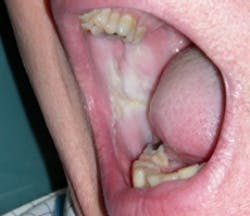

Morsus in Latin means bite. Morsicatio buccarum is biting or chewing of the buccal mucosa; morsicatio labiorum is chewing the lip area (see Figure 2) and morsicatio linguarum is chewing on the borders of the tongue (see Figure 3). The habit may be chewing, biting, or chronic pressure of the tissues. Thicker areas of keratosis may be observed as noted in Figure 3 when the patient continually causes an assault on the oral tissues.